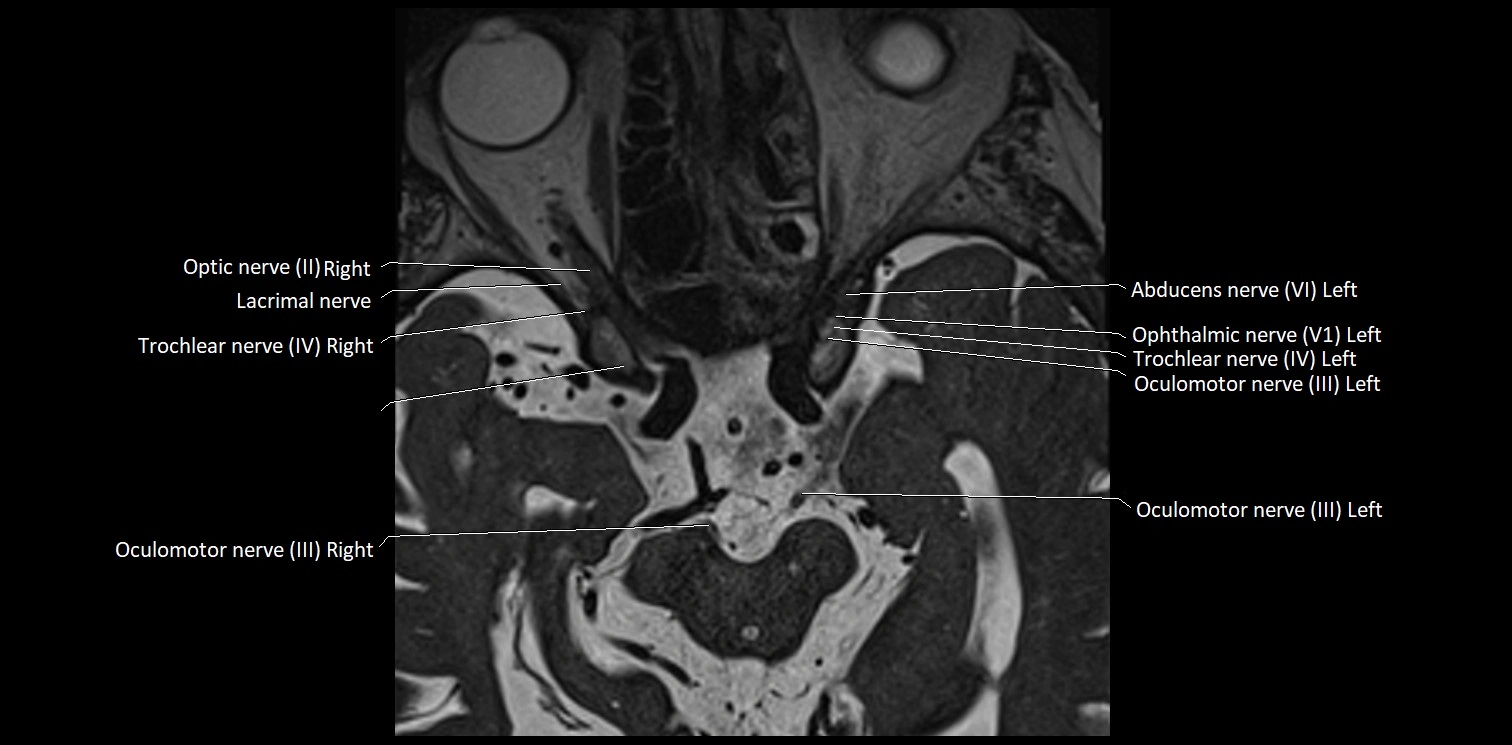

MRI images

image